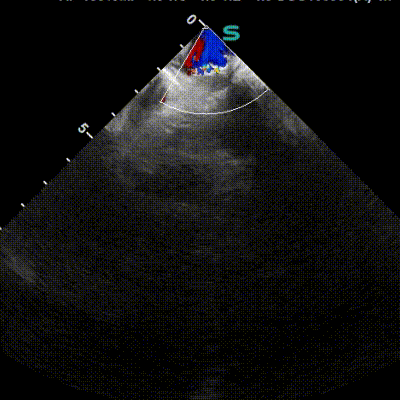

超声描述:经左侧肘正中静脉注入造影剂后:右房、右室顺序显影,右心充盈良好,静息状态下左心未见气泡影;嘱咐患者Valsalva动作,右房显影即刻放松,连续观察15个心动周期,3个心动周期内,左心可见过性“云雾状”微泡进入左房(>50个/帧)。

超声提示:右心声学造影:阳性(心内水平右向左分流,巨量)。

患者1 年前无明显诱因出现失眠、头昏,伴焦虑、多思,磁共振平扫(颅脑)MRI 示脑干左侧份异常结节影,左侧半卵圆中心及右侧侧脑室后角旁见结节状腔隙性梗死 / 缺血灶,超声检查提示右心声学造影阳性,存在心内水平右向左分流(巨量)。综合考虑病情,经充分沟通后,患者主动选择可降解PFO封堵器进行封堵手术,术后患者头晕症状明显缓解。